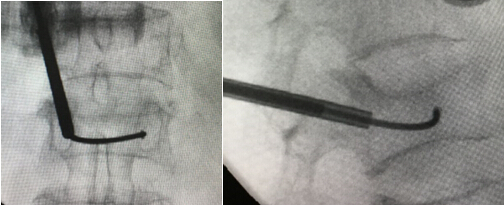

术中正侧位透视显示弯角的注射管

术中透视L1椎体骨水泥分布满意,无明显渗漏